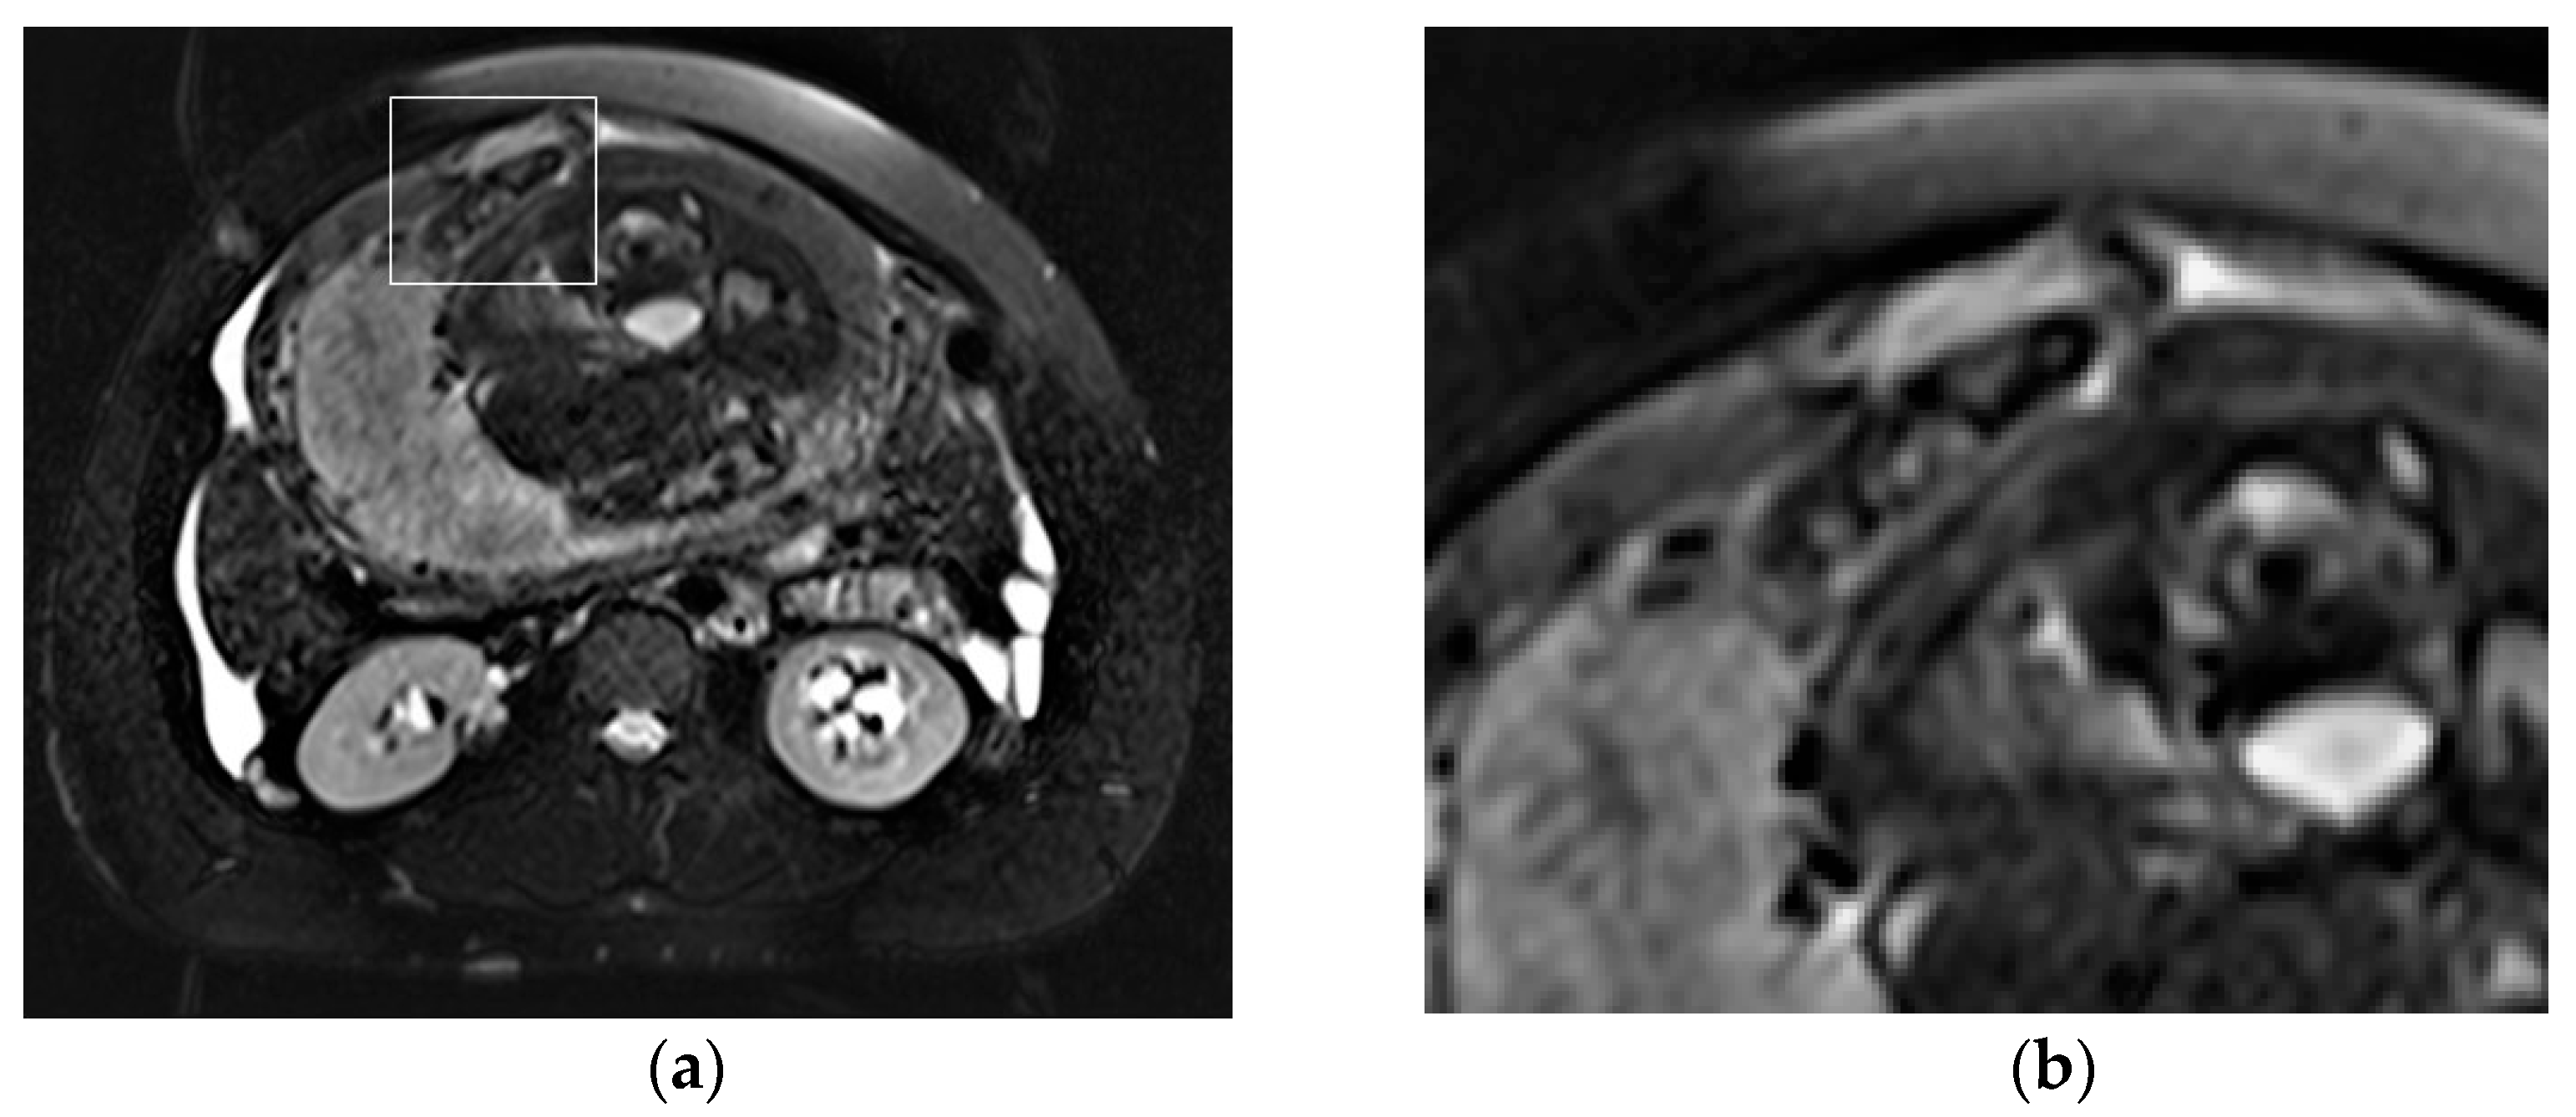

In peripartum and during delivery, the acute clinical presentation of UR obviates the need for diagnostic imaging, which is most helpful when this complication occurs earlier in the pregnancy. US is the first method of choice, owing to its availability, cost effectiveness, and lack of ionizing radiation. While transabdominal US provides a wider field of view (FOV) and better general evaluation of the pregnant status, transvaginal US allows more accurate assessment of the reproductive system [88]. In expert hands, US may depict the site of perforation, as an anterior hypo/anechogenic line, extending to the serosa; the uterus appears bulky and empty, while the placenta and fetal parts are located in the abdominal cavity. The ancillary non-specific findings of UR, such as concomitant hemoperitoneum and extrauterine hematoma, are the most commonly detected. On Color Doppler imaging, vascularity at the site of uterine breach may be decreased due to intra-myometrial hematoma [85,89,90]. When US in inconclusive, MRI represents a problem-solving tool with a larger FOV and improved visualization of the uterine wall, helping to diagnose antepartum UR (Figure 5).

Figure 5. Acute abdominal pain in a 37-year-old patient at 34 weeks of gestation, with the suspicion of acute appendicitis. Axial T2-weighted fat-sat image (a) shows a full-thickness tear within the anterior uterine wall that also includes the uterine serosa, with herniation of the hand of the fetus through the defect, as highlighted by the square (b).

On T2-weighted images, the placenta and amniotic sac are hyperintense, whereas the myometrium is isointense to muscle, allowing the detection of the tear itself. The high-contrast-tissue resolution of MRI provides for the depiction of fetal parts and extrauterine membranes. On T1-weighted images, hyperintensity of blood products identifies the hemoperitoneum [4,7,91].